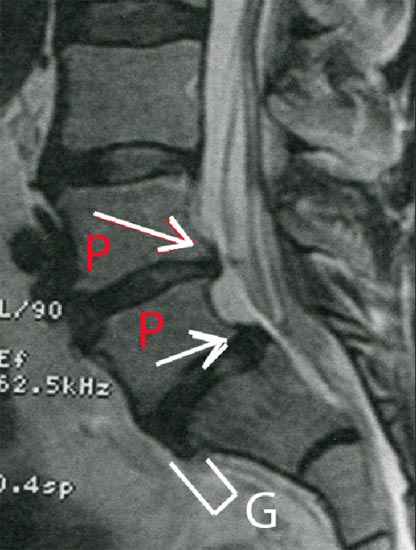

Depuis des mois je bataille comme je peux avec ce dispositif pour tenter de réduire mes deux hernies discales. C'est du long terme. Avec l'âge et surtout la pire des choses : un excès de sédentarité, les haubans musculaires de la colonne fondent. Les disques, déshydratés, s'affaissent et donnent des " protrusions ".

**P : protrusions discales. G : glissement vertébral ( spondylolistésis ) **

Il est aussi nécessaire de contrôler son poids. Prendre des kilos équivaut à porter un sac à dos et votre colonne vertébrale, de même que vos articulations des genoux et de hanches vous le rappellent au passage. Ce bassin est un excellent moyen d'entretien pour gens âges, à condition d'aimer l'eau. Disposer d'une salle de musculation chez soi est une bonne chose. Il y a tous les gadgets possibles imaginables : les vélos d'appartement. L'aquagym est un système de musculation complet. Pour accentuer l'effort sur les jambes, vous pouvez mettre des palmes. Cette musculation s'effectue aussi sans efforts de compression des articulations. C'est " mobiliser sans effort ". Je sais que des kinés liront cette page, et se diront " pourquoi être-ce que je n'installerais pas cela dans mon cabinet ? ". En doublant ce bassin on peut y faire travailler quatre personnes de front. Dans chaque section, un client fait sa gym en position verticale, dans le " grand bain ", tandis que l'autre se livrera à d'autres exercices dans un mètre d'eau. Bien sûr, dans un cabinet de kinésithérapie, l'eau s'évaporera pendant un nombre d'heures plus important et on ne pourra pas installer son bureau juste à côté.